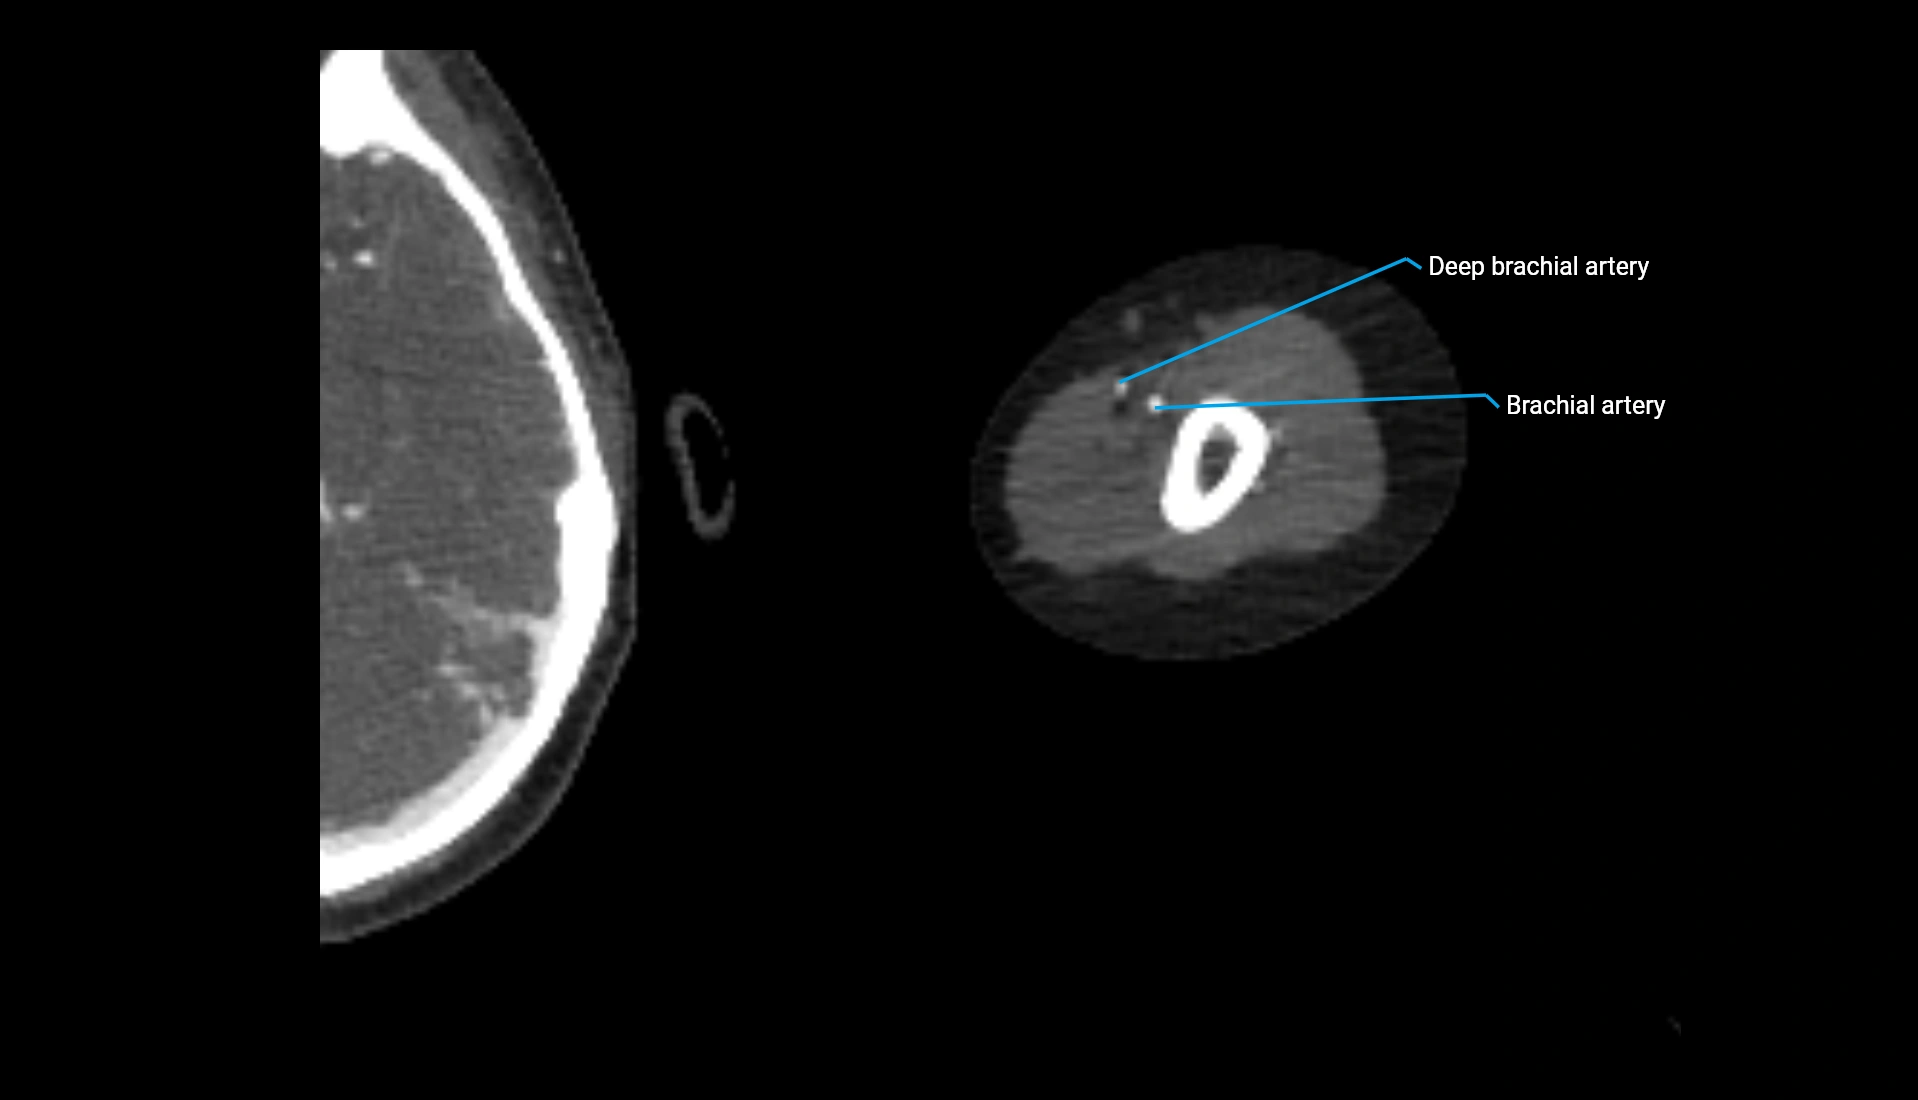

CT Appearance

Non-Contrast CT:

• Cortex: High-density, sharply defined

• Subchondral bone: Dense cancellous matrix

• Articular surface: Smooth concave contour articulating with the capitellum

• Excellent for evaluating bone integrity, alignment, and subtle fractures

Post-Contrast CT:

• Bone: No enhancement

• Joint capsule and synovium: Mild enhancement outlining the joint

• Improves contrast between soft tissues and bony margins

• Useful in detecting subtle joint abnormalities or postoperative changes